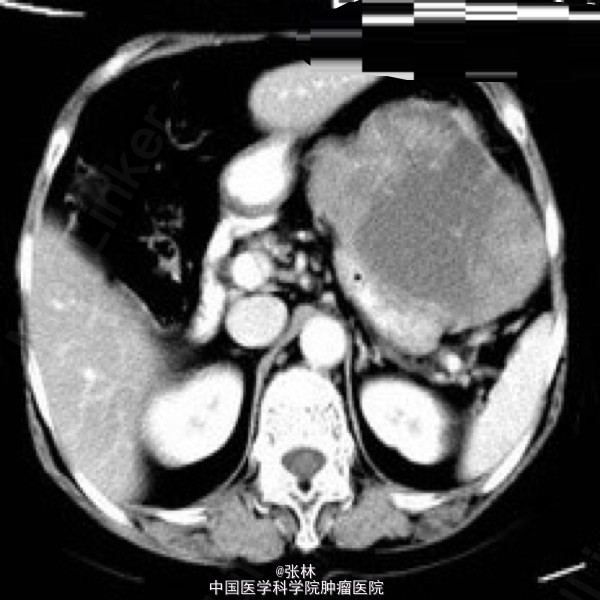

病史:女,65岁,上腹不适3年。

CT表现:胃体部前外侧壁可见一外生性肿物,体积大,形态较规则,边界清楚,肿物与邻近胃壁不可分,胃腔受压变扁;平扫呈较均匀等或略低密度,增强扫描明显不均匀强化,周边实性部分呈渐进性强化,中心可见片状无明显强化的更低密度区域。

术中:肿物位于胃前壁体底交界处,约12X10X10cm,占据上腹大部分,于肝左外侧叶稍粘连,肿物呈暗红色,质硬,肿物附近胃壁颜色、质地正常。 病理诊断:胃高度恶性间质瘤。